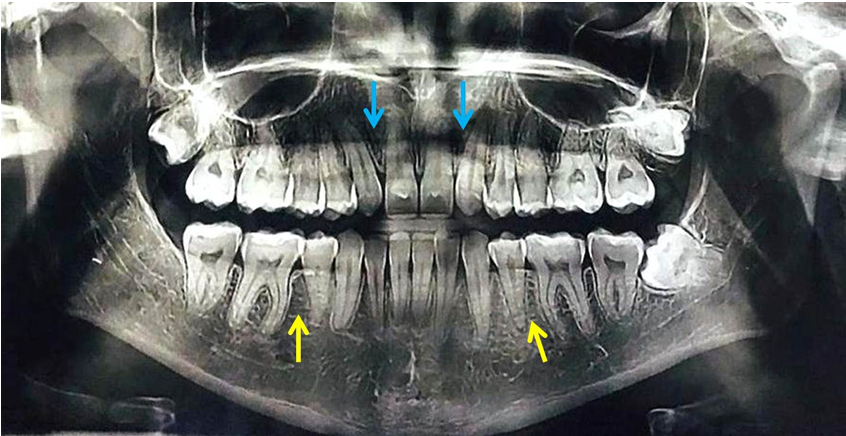

Idiopathic congenital dental agenesis is an uncommon clinical entity rarely found in a normal individual. This condition may involve either primary or permanent dentition, can occur in single or include multiple teeth. Diagnosis and management of tooth agenesis is very important to provide appropriate patient care. The present article briefly describes occurrence of bilateral idiopathic congenital tooth agenesis involving permanent maxillary lateral incisors and bilateral mandibular second premolars found in a 25-year-old Indian male patient.

Literature search shows congenital agenesis of teeth occurring in a non-syndromic patient without any particular etiology which can be referred as an idiopathic nature. This clinical entity can involve any dentition either primary or permanent or any tooth [1]. The most commonly seen congenitally missing teeth are the third molars followed by maxillary lateral incisors and mandibular second premolars. There is no exact true etiology behind the occurrence of tooth agenesis; however, various genetic and environmental factors have been suggested as causative factors for tooth agenesis in humans [1]. The present article enlightens occurrence of bilateral idiopathic congenital dental agenesis involving maxillary lateral incisors and mandibular second premolars detected in an Indian patient following routine clinical and radiographic examination. Details of the present case are elaborated in Table 1 and Figure 1.